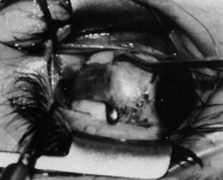

Parks47,48 subsequently developed an alternate technique to address some of the technical problems he experienced with the Berke technique. A superior temporal fornix incision is made through conjunctiva and Tenon's capsule down to bare sclera, and the superior rectus is hooked through this incision. The superior rectus then is exposed by reflecting the intermuscular septum, Tenon's capsule, and conjunctiva over the toe of the large hook. The nasal border of the superior rectus is exposed by temporal traction on the muscle hook, securing the superior rectus insertion while the conjunctival wound is further displaced nasally with two Stevens muscle hooks or a Desmarres retractor. The superior oblique tendon is identified visually as a cord of parallel fibers seen coursing from beneath the nasal border of the superior rectus approximately 8 to 12 mm posterior to its insertion. This technique allows isolation of the superior oblique tendon under direct visualization. Once isolated in this way, tenotomy or tenectomy of the tendon can be completed with almost no violation of surrounding intermuscular septum or Tenon's capsule. Therefore, once the tendon is cut, the cut ends separate but maintain their normal anatomic relationships. Because they are still embedded in intermuscular septum and surrounding Tenon's tissue, they continue to provide a weakened but vectorially normal force on the globe, thereby reducing the incidence of consecutive superior oblique palsy.49 At the completion of the procedure, all instruments are removed from the eye. The exaggerated forced duction test is repeated to verify that all superior oblique tendon fibers have been transected.

The advantages of the Parks technique over others described include: (a) direct visualization of the entire tendon before isolation with the muscle hook, thereby eliminating the riskier blind hooking of the tendon, with its increased risk of incomplete tendon isolation, violation of the orbital fat, or inadvertent transection of the superior rectus muscle;50 (b) transection of the cordlike tendon nasal to the superior rectus, where the weakening effect is more predictable; and (c) transection with minimal or no dissection of surrounding intermuscular septum, thereby preventing uncontrolled scarring with reattachment of the superior oblique tendon to the sclera in an unwanted location, or alteration of the tendon's course, which might change its vector of action on the globe. A modification of the Park's technique, preferred by the authors, is described in the following.49 Additional information about the superior oblique tenotomy or tenectomy technique is provided in another chapter.